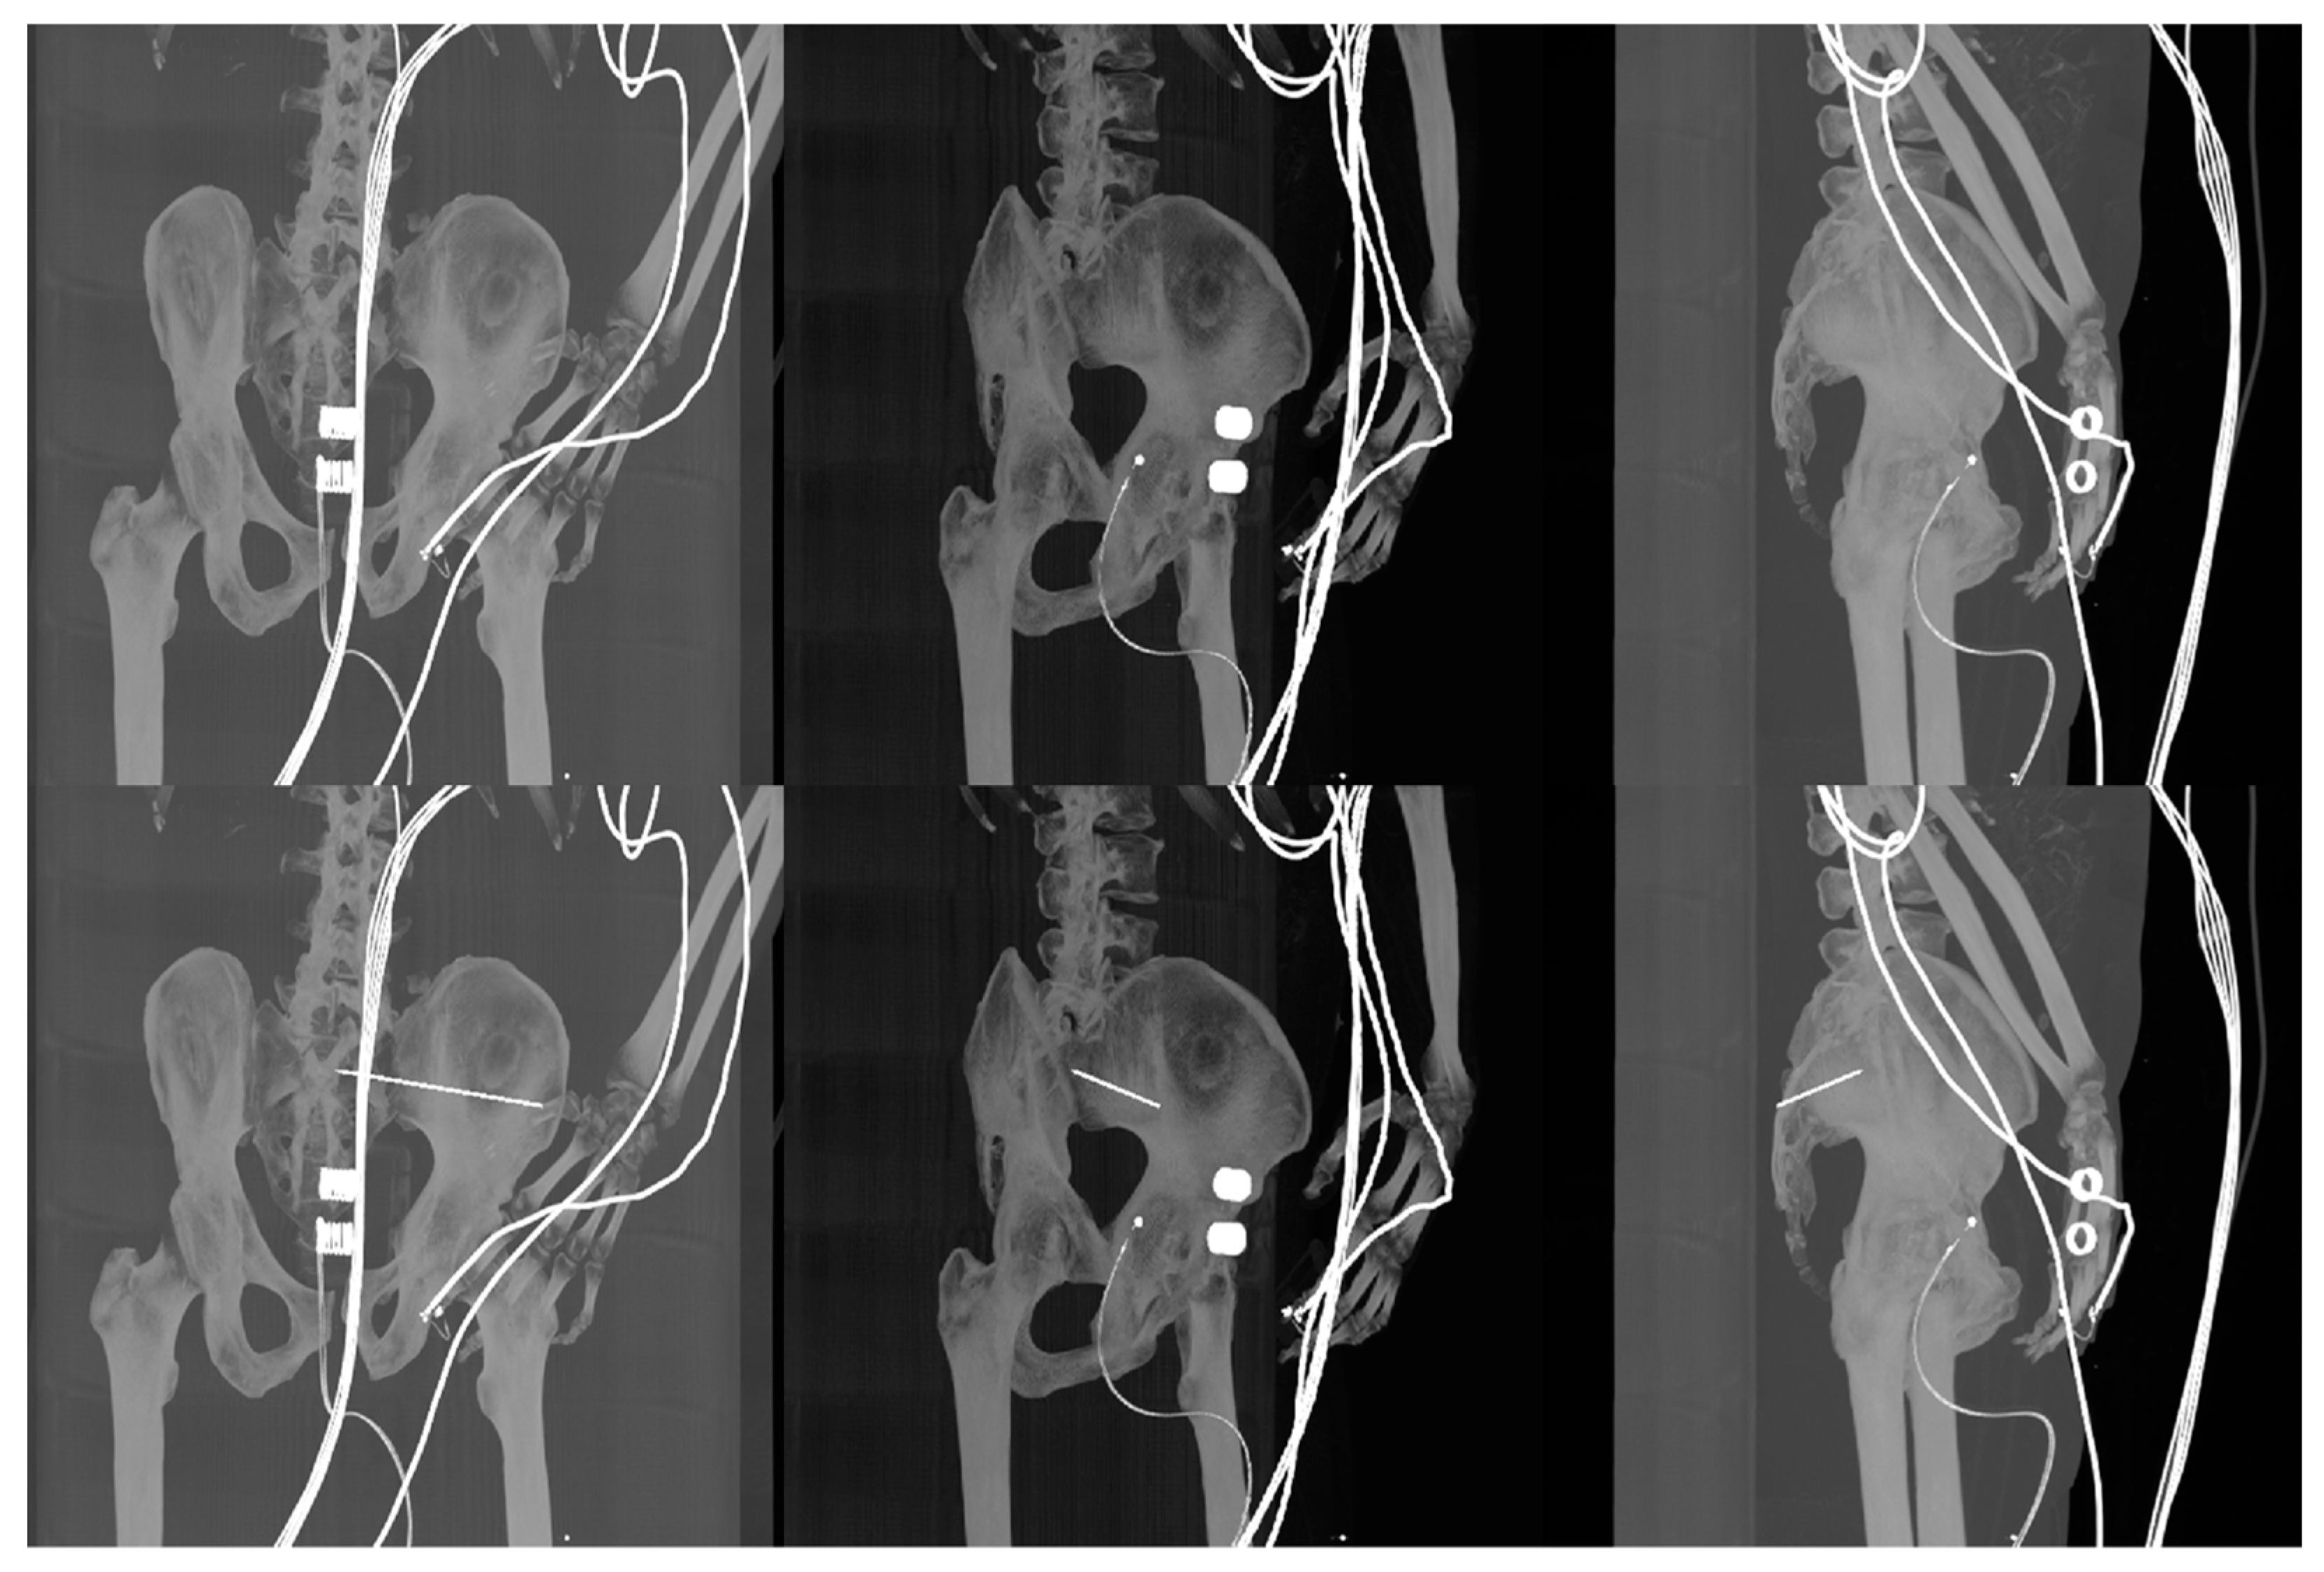

- Reconstructed DDR projections with virtual iliosacral screw

- Multimodal (X-ray/CT) image registration for optimal CT slice selection according to the reference X-ray image.

- Generation of 3D models of the pelvis

- Generation of digitally reconstructed radiograph (DRR) projections

- Multimodal image registration of DRR projections to a reference X-ray image